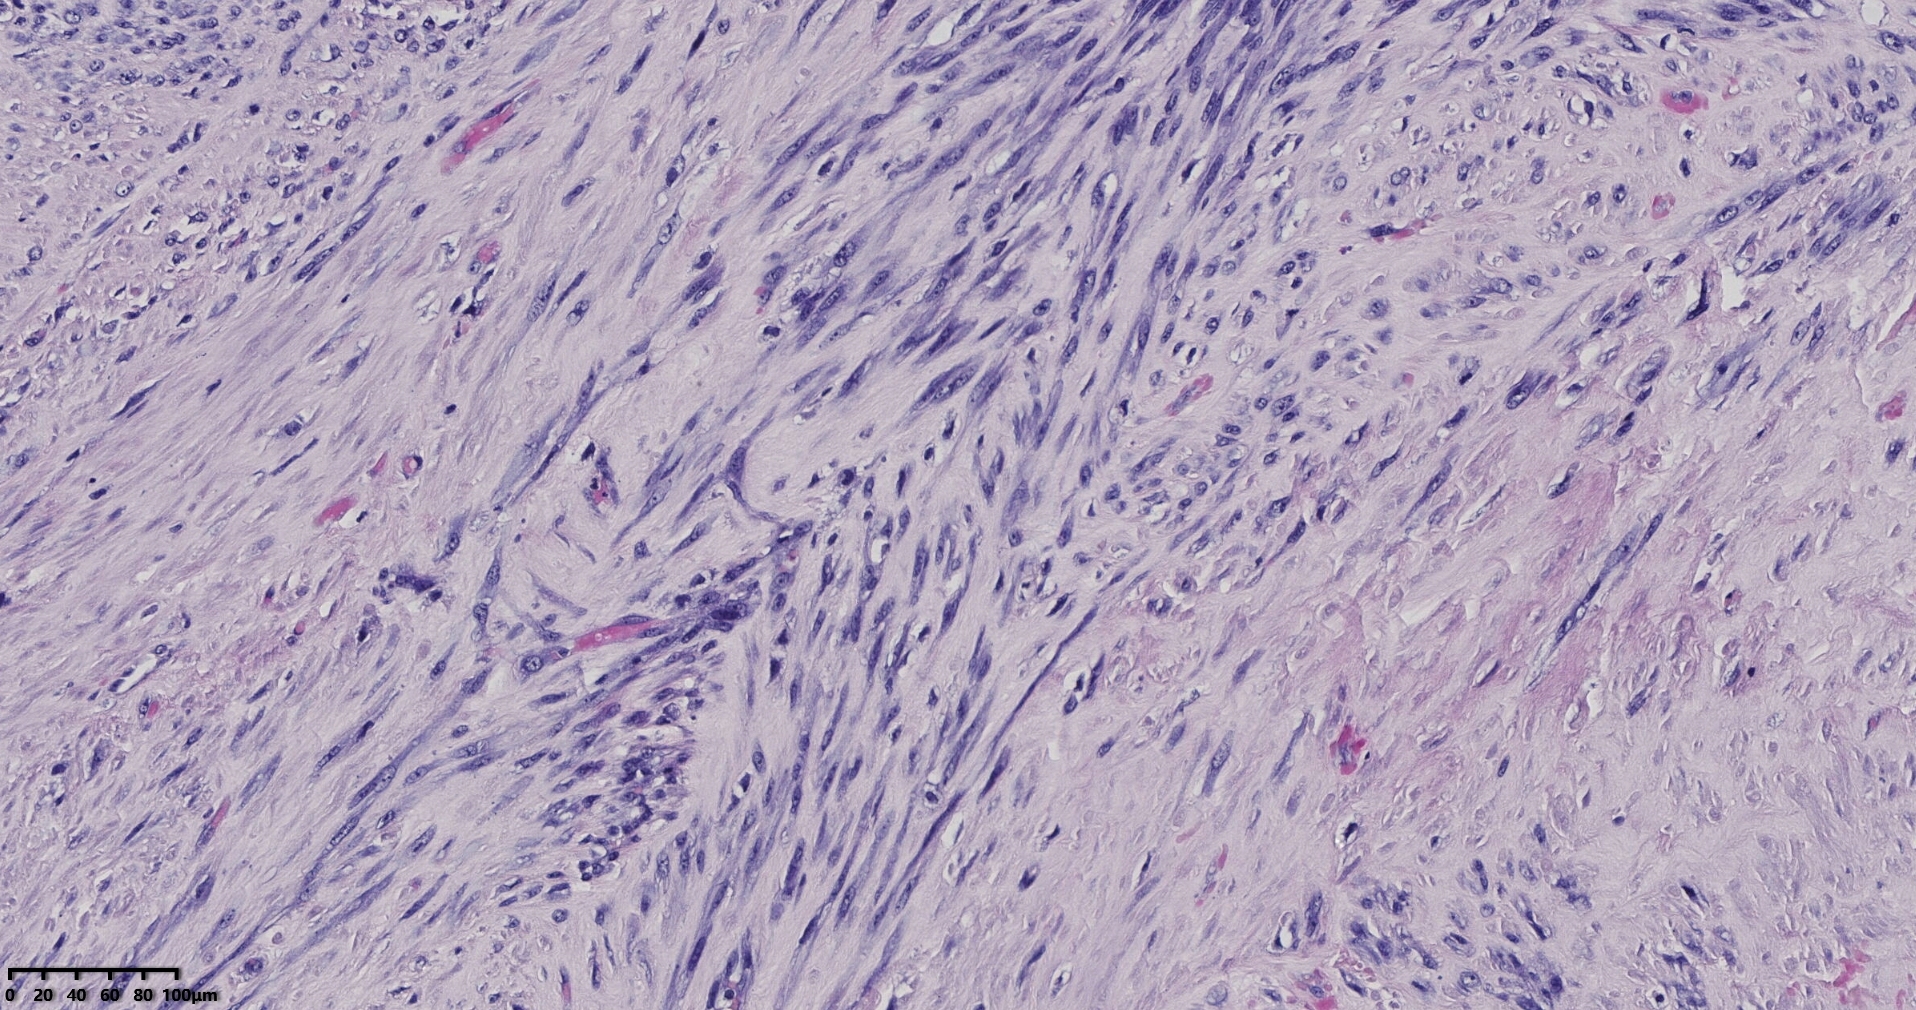

镜下所见小肿物无特殊,大肿物瘤细胞密集,中心区有变性、坏死,瘤细胞核有异型性。大肿物补充取材,发现,部分区域切面灰黄,这个区域,瘤细胞更密集,异型性更显著。肿物边缘有薄层正常平滑肌组织被覆,靠近边缘瘤细胞最密集,局部瘤组织内小血管较丰富。